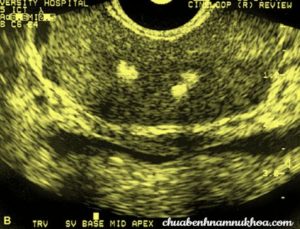

Hình ảnh nốt vôi hóa

hình ảnh siêu âm